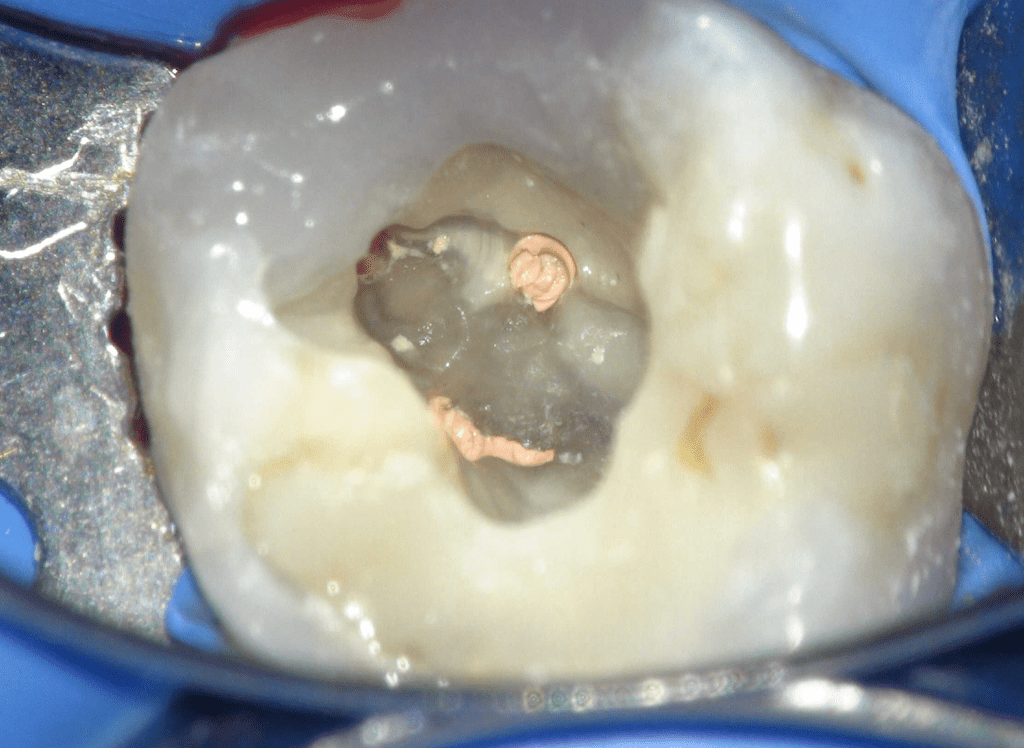

Fisura, remoción amalgama para explorar